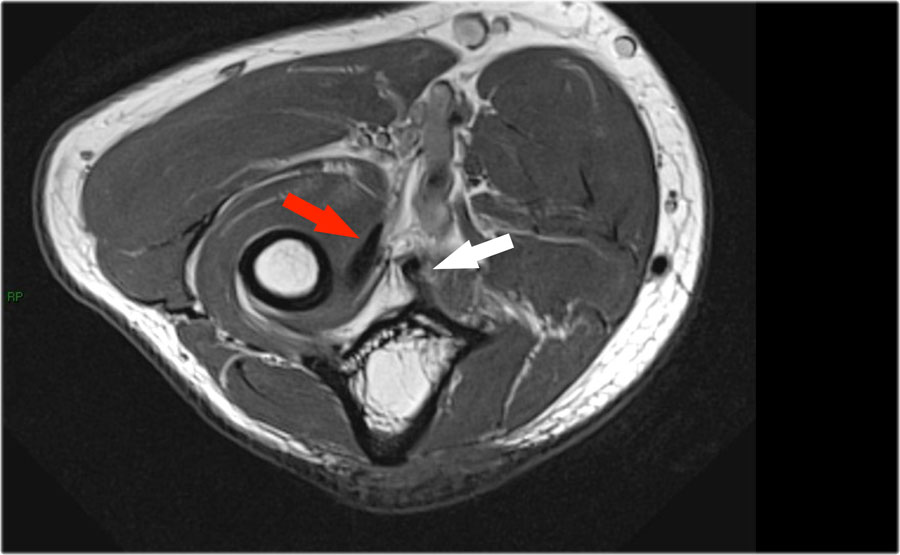

Cuộn qua các hình ảnh cắt ngang của gân cơ nhị đầu từ chỗ nối cơ-gân đến điểm bám tận trên lồi củ xương quay.

Bệnh lý của gân cơ nhị đầu đoạn xa rất giống với bệnh lý của gân Achilles.

Có thể gặp thoái hóa gân, rách một phần và rách hoàn toàn có hoặc không có sự co rút.